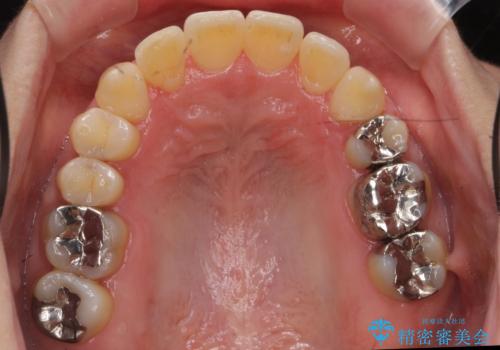

40代の矯正 八重歯を綺麗に

上の前歯が内側に入っているクロスバイトは、笑った時に影になってしまい、かなり目立ちます。

内側に入っている前歯を外に出すだけで劇的に印象が変わります。